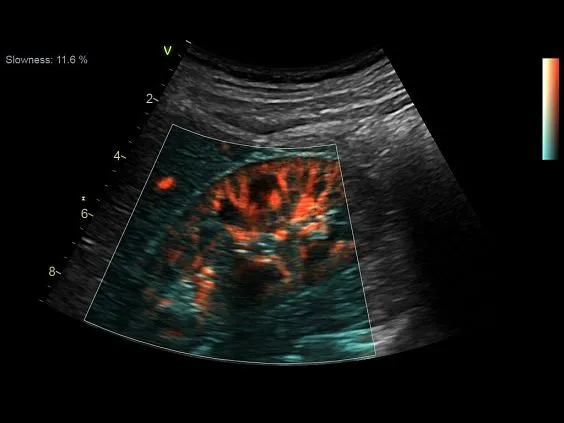

- Advanced Vascular B-Flow and BFI

- Advanced Vascular B-Flow and BFI

- Ангиология

- Бескомпромиссный уровень качества визуализации как в двухмерном режиме, так и в режиме объемной реконструкции, а также гарантируя высочайшую чувствительность при цветовом картировании кровотока и допплерографии.

Экспертное качество изображений при проведении 2D TTE исследований и при обычной трансторакальной эхокардиографии дает возможность проводить сложные кардиологические исследования и получать достоверные результаты для назначения эффективного лечения.

Благодаря своим техническим возможностям система Vivid S70 позволяет получать достоверные данные для количественной оценки даже при проведении исследований пациентам с избыточным весом или пациентам состояние которых затрудняет проведение диагностики, а технология датчиков XDclear работающая в паре с платформой cSound гарантирует беспрецедентный уровень качества изображений.